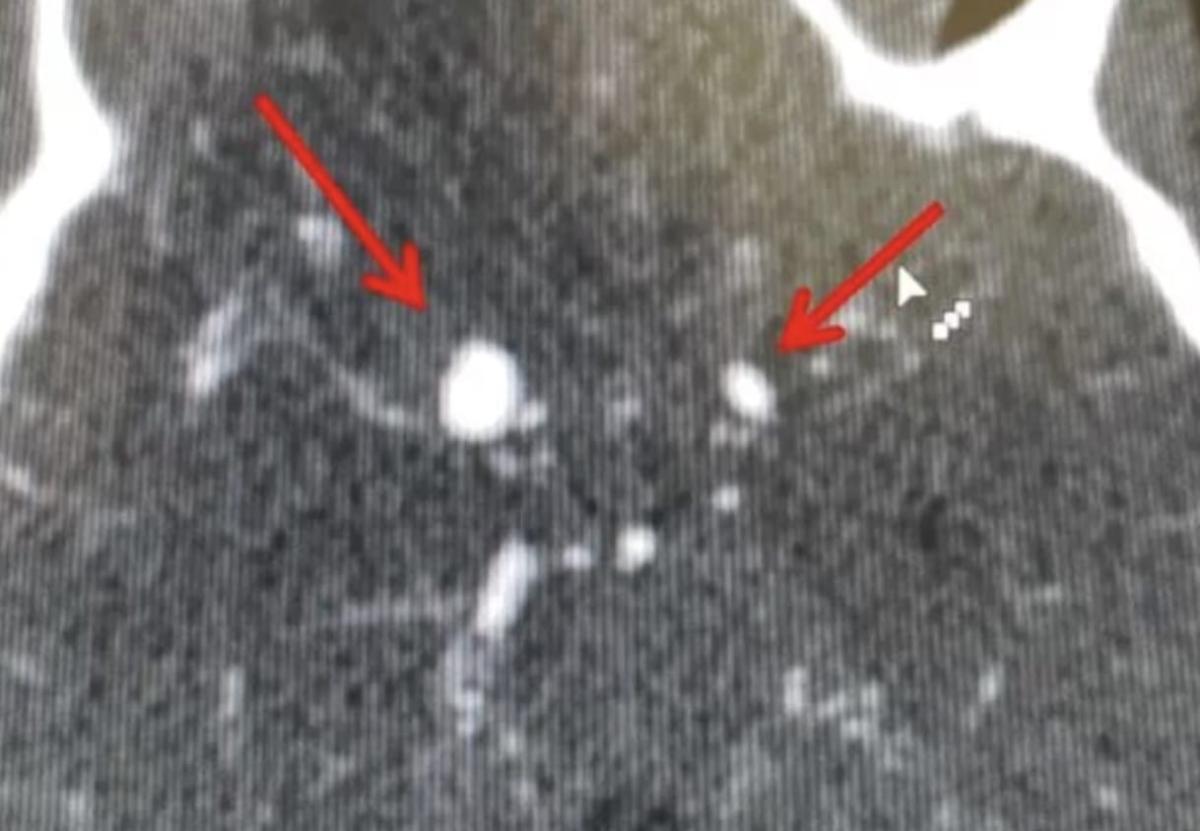

Ένα ανεύρυσμα εγκεφάλου είναι μια σιωπηλή αλλά εξαιρετικά επικίνδυνη κατάσταση, που συχνά δεν δίνει καμία ένδειξη μέχρι τη στιγμή που γίνεται απειλητική για τη ζωή. Πρόκειται για διόγκωση ενός αιμοφόρου αγγείου μέσα στον εγκέφαλο, η οποία ασκεί πίεση στους γύρω ιστούς ή, εάν σπάσει, προκαλεί αιμορραγία και εγκεφαλική βλάβη.